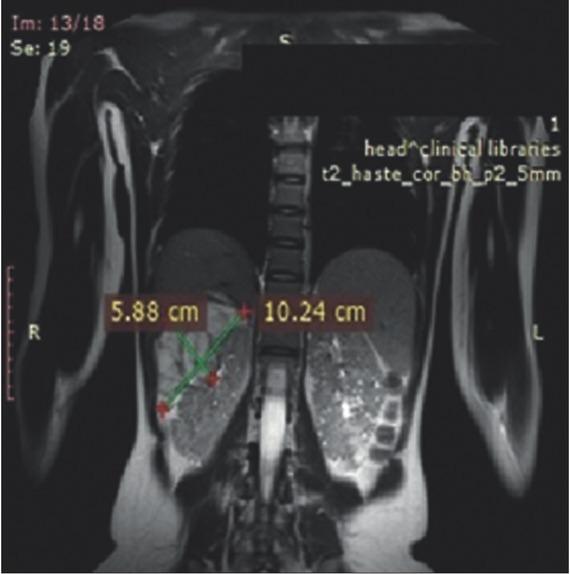

Tuberous sclerosis complex (TSC) is an autosomal-dominant multi system disorder. The genetic basis of the disorder is mutations in the or gene, which leads to over activation of the mammalian target of rapamycin (mTOR) protein complex and results in development of benign tumors in different body systems such as brain, skin, lungs and kidney. The mTOR inhibitors are presently the main treatment option for patients with TSC. We here report a 21-year female patient with large bilateral angiomyolipoma (AML) in both kidneys with longest diameter more than 12.3 cm and subependymal giant cell astrocytoma (SEGA). Treatment with everolimus (EVE) was initiated at a dose of 10.0 mg/day and continued during the following 3 years. Magnetic resonance imaging (MRI) was performed before treatment with everolimus was initiated, and consequently at 12 and 36 months for follow-up of the efficacy of the treatment. After 3 years, the total size of largest AML decreased by ~24.0% in the longest diameter. A reduction of the total size of SEGA was also observed. The most common adverse effect of treatment was stomatitis grades 3 to 4 and one febrile episode associated with skin rash that required a reduced dose of EVE. In conclusion, the everolimus treatment improved even such a large renal AML and the effect persisted during the long-term administration with a small number of adverse effects. A positive effect was observed on the brain tumor as well.

结节性硬化症(TSC)是一种常染色体显性遗传的多系统疾病。该疾病的遗传基础是 或 基因发生突变,这会导致雷帕霉素哺乳动物靶点(mTOR)蛋白复合物过度激活,进而在脑、皮肤、肺和肾等不同身体系统中引发良性肿瘤。mTOR 抑制剂目前是 TSC 患者的主要治疗选择。我们在此报告一名 21 岁女性患者,双侧肾脏患有直径超过 12.3 cm 的巨大血管平滑肌脂肪瘤(AML)以及室管膜下巨细胞星形细胞瘤(SEGA)。以 10.0 mg/天的剂量开始使用依维莫司(EVE)治疗,并在接下来的 3 年中持续使用。在开始使用依维莫司治疗前进行了磁共振成像(MRI)检查,并在治疗 12 个月和 36 个月时进行了随访,以评估治疗效果。3 年后,最大 AML 的最长直径总大小减少了约 24.0%。SEGA 的总大小也有所减小。治疗最常见的不良反应是 3 至 4 级口腔炎以及一次与皮疹相关的发热发作,这需要减少依维莫司的剂量。总之,依维莫司治疗改善了如此大的肾 AML,且在长期给药期间效果持续,不良反应较少。对脑肿瘤也观察到了积极效果。